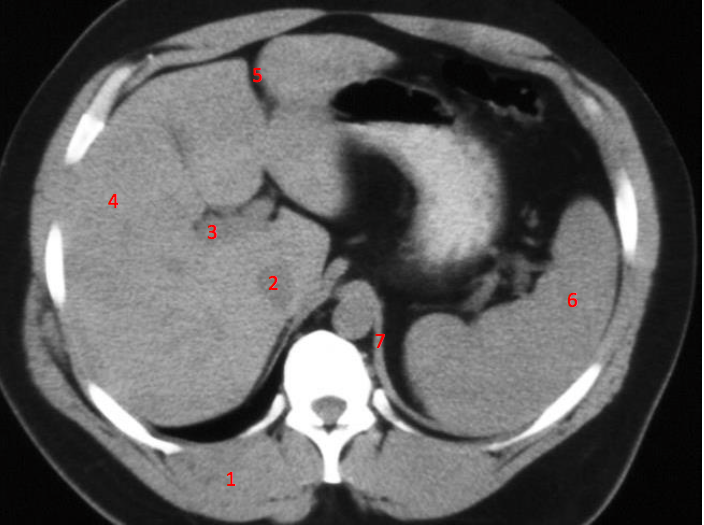

Number 1?

R Kidney

Number 2?

IVC

Number 3?

Gall bladder

Number 4?

Rectus abdominus

Rt lobe of liver

Number 6?

Stomach

Descending colon

Number 8?

Bladder